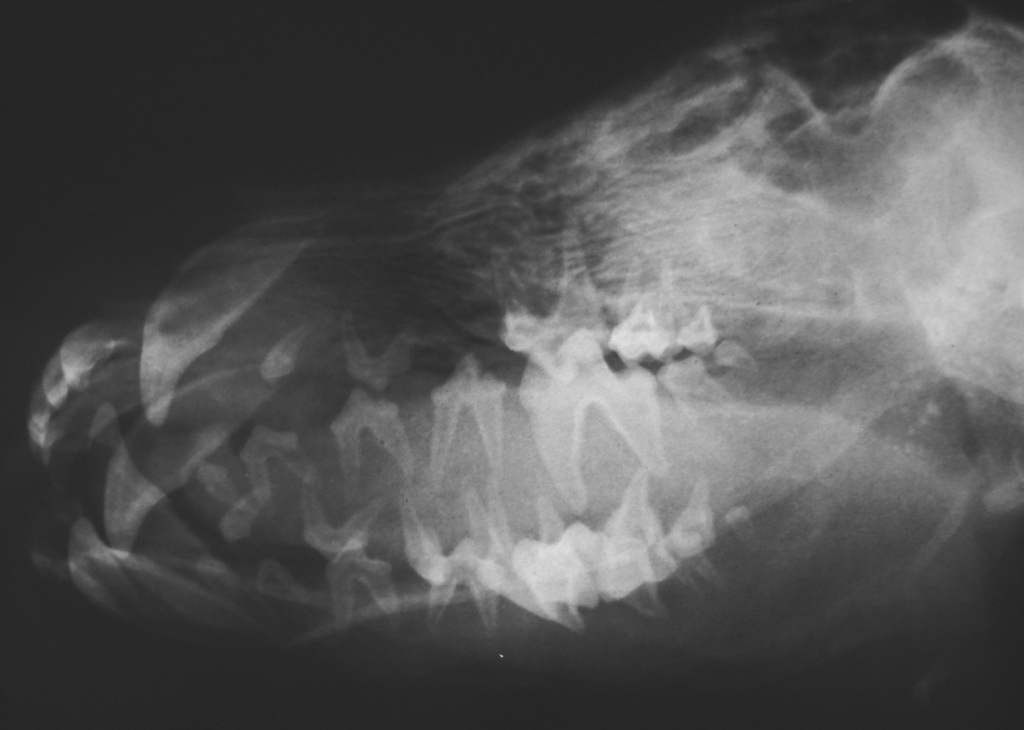

b Lateral - oblique view

.jpg)

On both views the bone has a radiolucent appearance. This is homogenous and does not appear to be

lytic or have permeative lysis. All the teeth are well mineralised and gives the appearance that

they are floating in air.